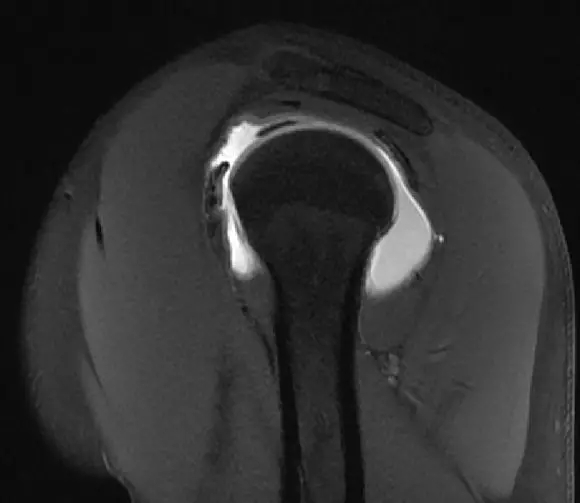

到这个层面,可以看到肩胛下肌建,冈上肌腱,冈下肌建